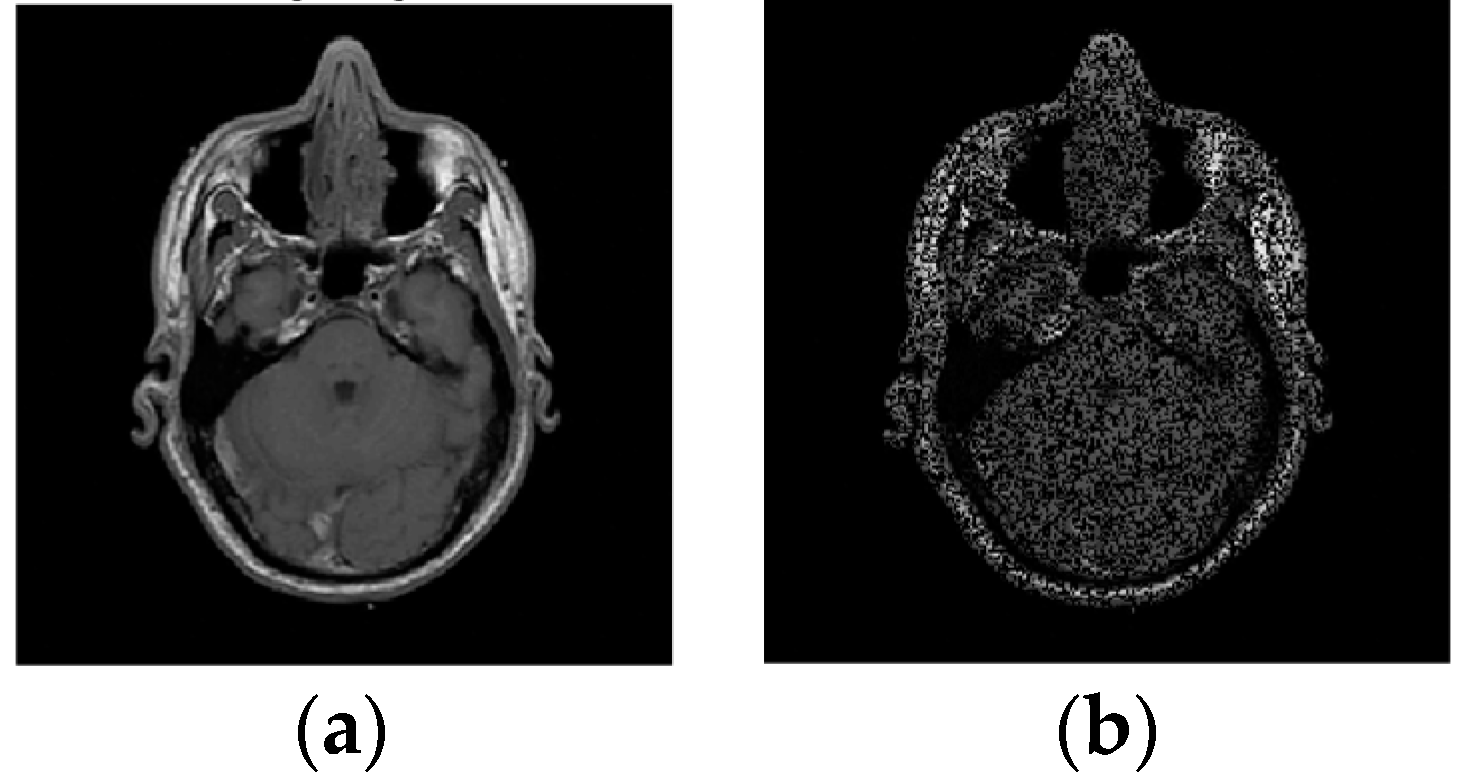

Example 2: In this example, the reconstruction efficiency is tested for the MRI image. Unlike the 1D case, the MRI image can be successfully recovered with almost all implemented algorithms. The percentage of missing samples is considered to be around 45. The original and image with missing samples are shown in Figure 6. The reconstruction procedures show that the radial-Fourier provided the best PSNR. However, the processing time is the longest using the radial-Fourier approach. The reconstruction results are shown in Table 1 and Figure 7.

Figure 6. The original (a) and image with missing pixels (b); 45% of pixels are unavailable.